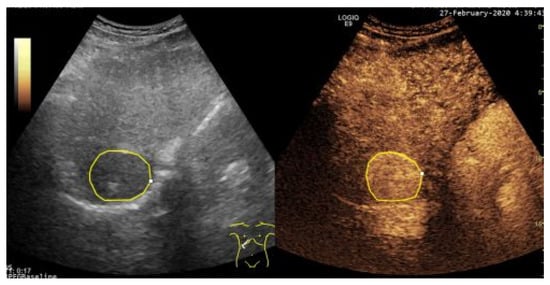

2.2.1. Data Preparation and Preprocessing